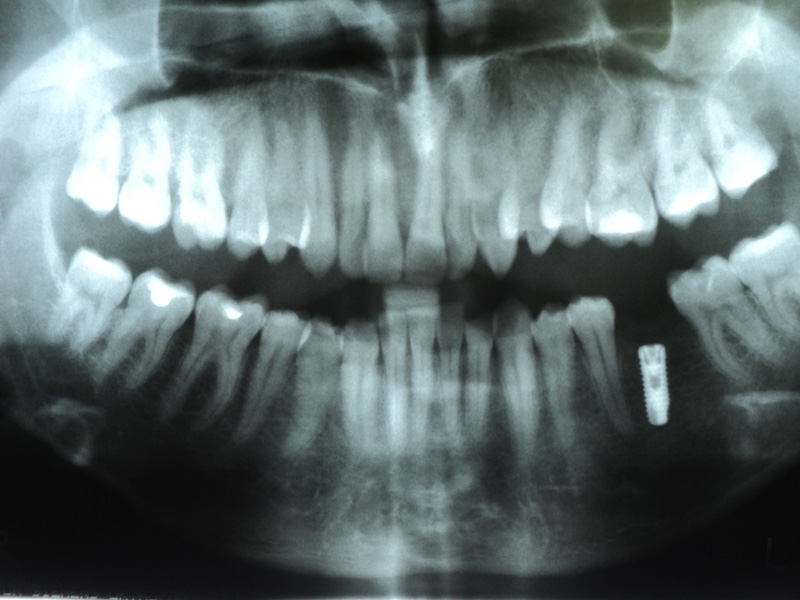

Implante - Galerie Foto

Caz I